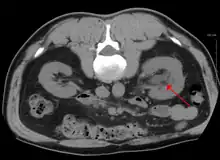

Left sided hydronephrosis in a person with an atrophic right kidney. Stent is also present (image below).

Left sided hydronephrosis, coronal view. Stent is also present.